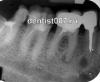

Stoney Опубликовано 29 августа, 2012 Поделиться Опубликовано 29 августа, 2012 Здравствуйте! У меня такая ситуация: в декабре 2009 ставили пломбу на предпоследний нижний зуб (который непосредственно стоит перед зубом "мудрости") и в этом же зубе удаляли нерв, чистили и пломбировали канал. После этого зуб меня не беспокоил. На днях (август 2012) зуб стал сильно болеть, а особенно при закрытии челюсти или постукивания по зубу. Обратилась к стоматологу: на рентгене видно, что под корнями зуба находится очаг инфекции (к сожалению не знаю как он называется по-русски, так как я сейчас не в России и обслуживали меня на английском языке). Снимки попробую забрать и выложить (тут так просто их не отдают), но картина приблизительно такая же, как в приложении, пятно воспаления находится под корнями жевательного зуба, и не четко видно, пошла ли она выше - то есть между корнями. Стоматолог отправила меня в клинику к более опытным врачам с просьбом попробовать лечение с помощью надреза десны и удаления воспалительного очага. При этом она прописала антибиотики и обезбаливающие, которые я сразу же начала пить. В клинику я попала только на 5й день после посещения стоматолога (тут все по записи), и соответственно это был 5й день антибиотиков. В клинике сказали, что на самом деле варианта 3: 1) почистить снова канал (в котором нет нерва) и посмотреть как пройдет процесс2) разрезать десну и удалить воспалившуюся часть3) удалить зубНо точно они сказать не могут, надо бы сделать панорамный снимок в 3D, на котором все будет хорошо видно. Снимок этот (а точнее 3D изображение) сделали, но мне не показали и сообщили, что единственный вариант - это удаление зуба, так как воспаление дошло до кости (действительно, я ощущаю боль вокруг кости челюсти и в правой части подбородка постоянно болит и трудно глотать).Скажите пожалуйста, можно ли поверить докторам из клиники или лучше обратиться к другим врачам? Очень хочется попробовать спасти зуб.И еще такое уточнение: в клинике меня записали на прием по удалению зуба аж на 24 сентября (то есть через месяц после начала приема антибиотиков). Я не понимаю: неужели мне целый месяц сидеть на антибиотиках? Второй вопрос: стоматолог, которая направила в свое время в клинику, сказала что может и сама удалить зуб намного раньше и что ей для этого не нужны изображения в 3D. Мне не совсем понятно, как она это будет делать, ведь надо наверное точно знать где очаг инфекции и как он распространен...Пожалуйста помогите! Кроме всего прочего у нас назначена свадьба на 13 октября, хотелось бы с этим все разобраться и дать зубу зажить до этой даты... Заранее спасибо! Ссылка на комментарий